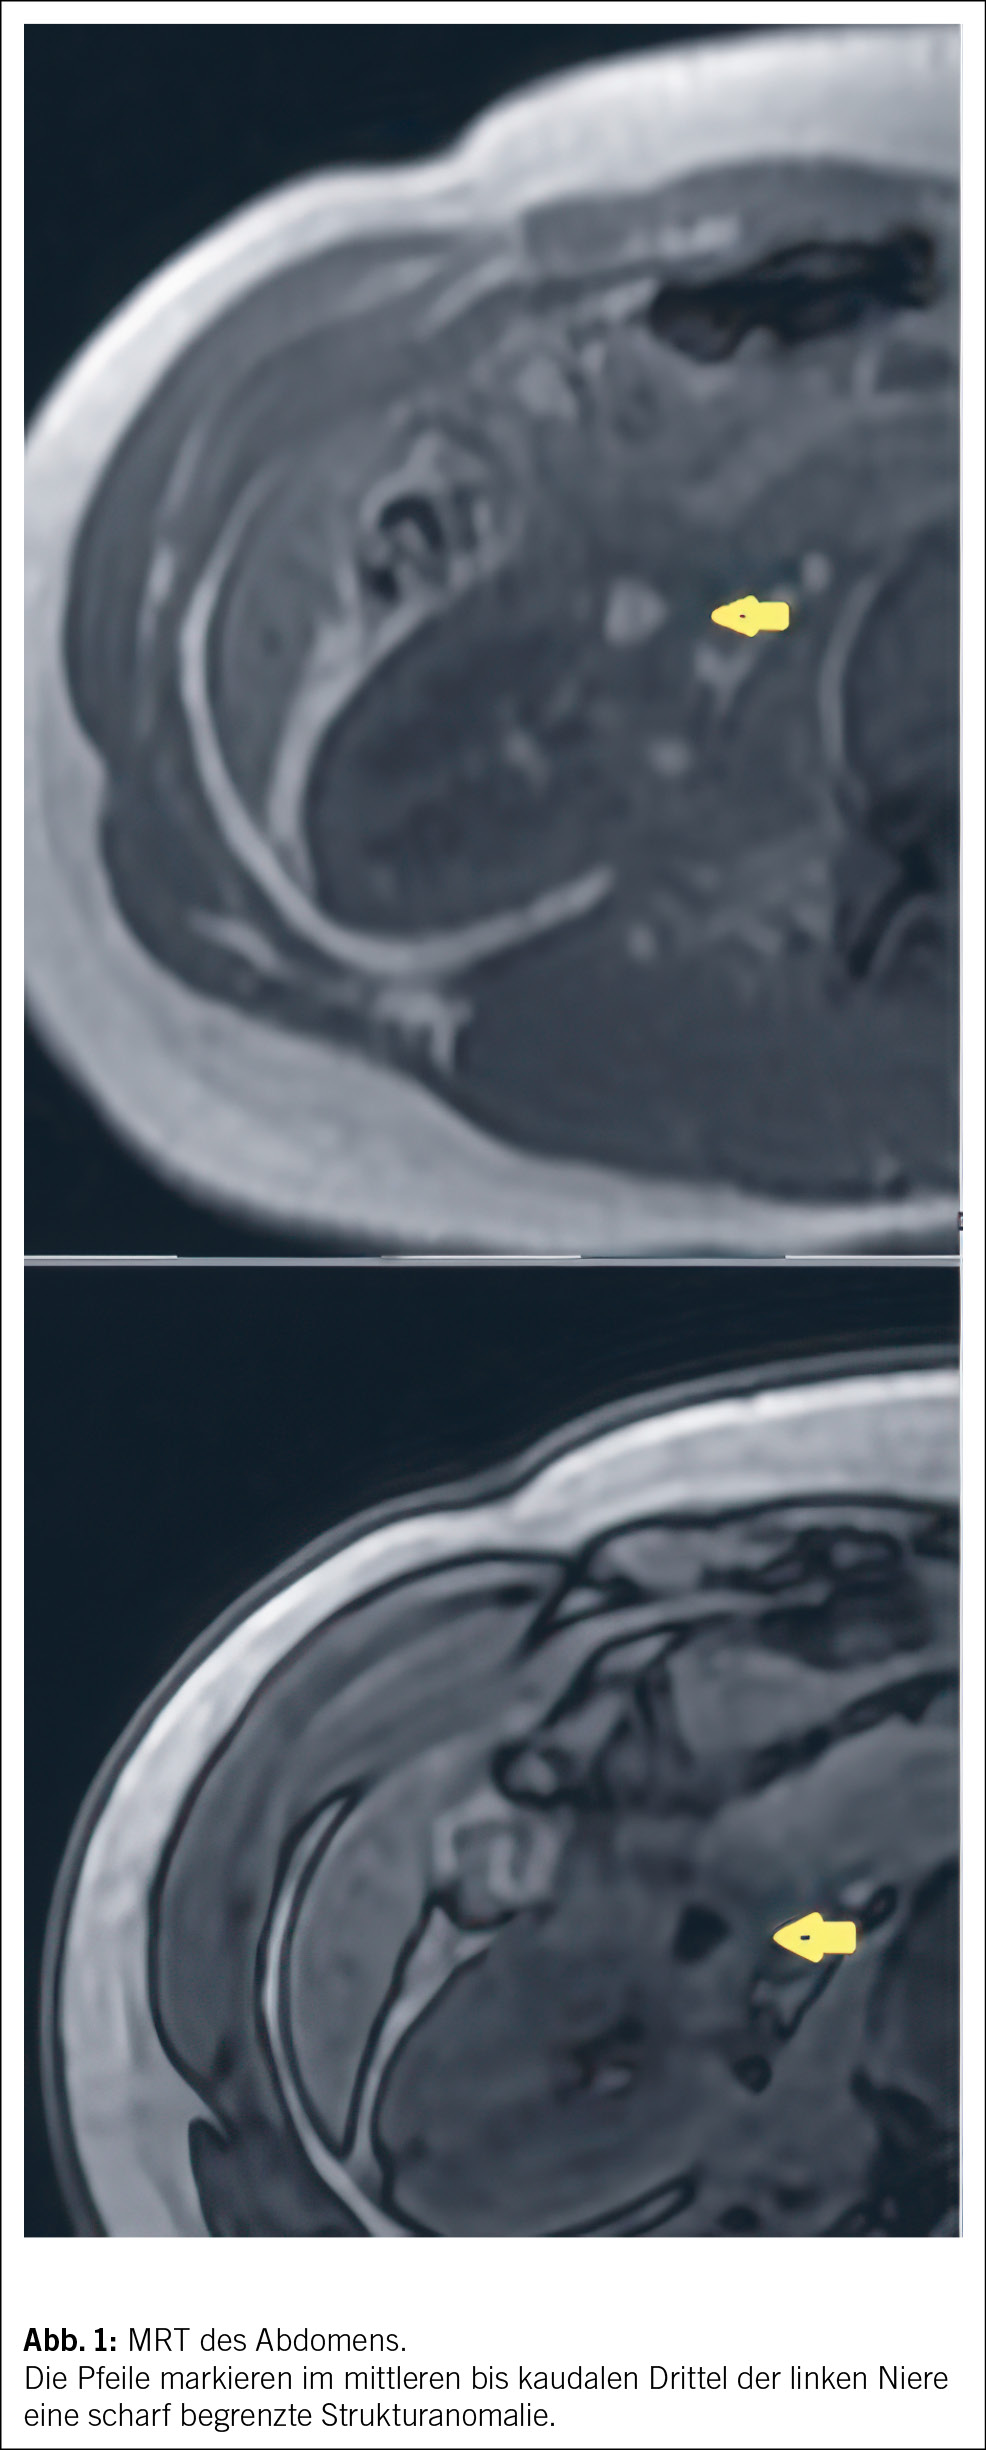

In der MRT-Untersuchung zeigte sich im Bereich des mittleren/kaudalen Drittels der linken Niere eine scharf begrenzte Strukturalteration mit einem Durchmesser von knapp 5 cm, die teilweise bis zum Nierenbecken reichte (Abb. 1). Definitive fettäquivalente Anteile konnten kernspintomographisch nicht eindeutig identifiziert werden, weshalb eine weitere Abklärung mittels Biopsie empfohlen wurde.